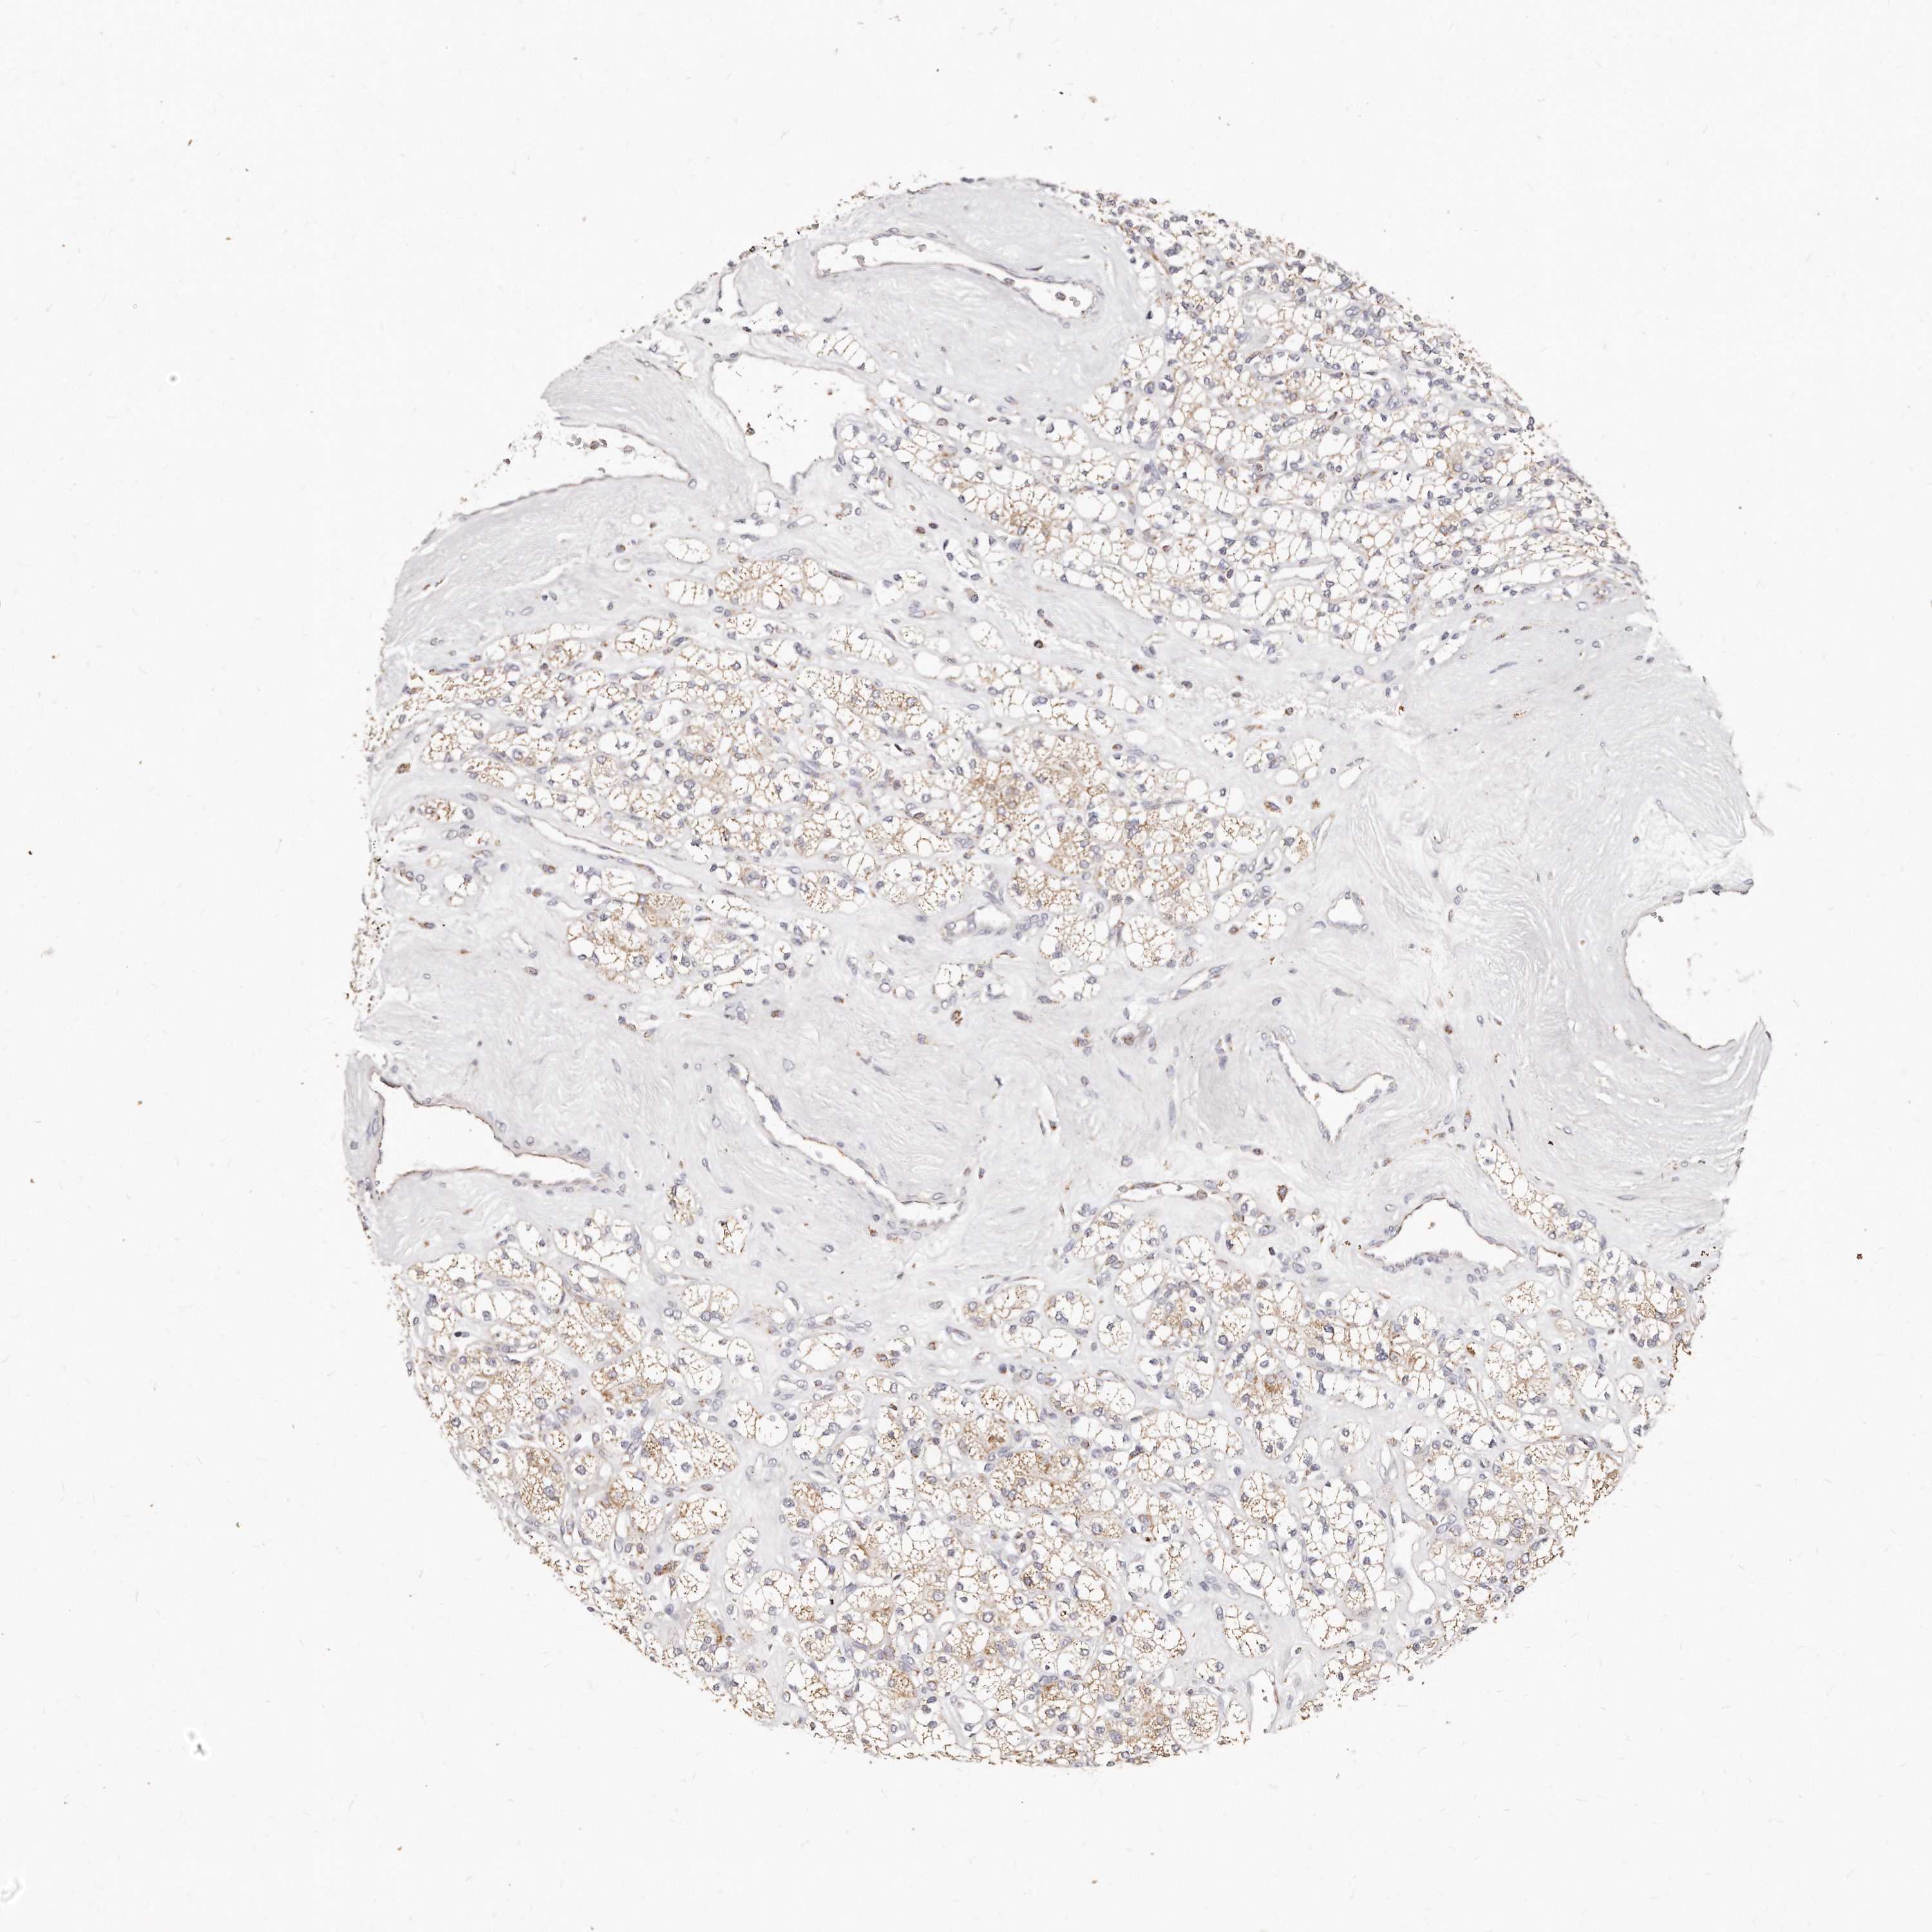

KIDNEY RENAL CLEAR CELL CARCINOMA (TCGA) - Interactive survival scatter ploti

The Survival Scatter plot shows the clinical status (i.e. dead or alive) for all individuals in the patient cohort, based on the same data that underlies the corresponding Kaplan-Meier plots. Patients that are alive at last time for follow-up are shown in blue and patients who have died during the study are shown in red.

The x-axis shows the expression levels (FPKM) of the investigated gene in the tumor tissue at the time of diagnosis. The y-axis shows the follow-up time after diagnosis (years). Both axes are complimented with kernel density curves demonstrating the data density over the axes. The top density plot shows the expression levels (FPKM) distribution among dead (red) and alive patients (blue). The right density plot shows the data density of the survived years of dead patients with high and low expression levels respectively, stratified using the cutoff indicated by the vertical dashed line through the Survival Scatter plot. This cutoff is automatically defined based on the FPKM cutoff that minimizes the p-score. The cutoff can be changed by dragging the vertical line or by entering a cutoff value in the square labeled "Current cut-off".

Under the Survival Scatter plot the p-score landscape (black curve; left axis) is shown together with dead median separation (red curve; right axis). Dead median separation is the difference in median mRNA expression between patients who have died with high and low expression, respectively. It is calculated as follows: median FPKM expression of dead patients with high expression - median FPKM expression of dead patients with low expression. This is intended to aid the user in visually exploring custom cutoffs and the associated p-scores and dead median separation.

Individual patient data is displayed and can be filtered by clicking on one or more of the category buttons on the top of the page. Categories describing expression level and patient information include: high, low, alive, dead, female, male and tumor stages. The scale of the x-axis can be toggled between linear and log-scale by clicking on the "x log" button. Mouse-over function shows TCGA ID, patient information and mRNA expression (FPKM) for each patient.

& Survival analysisi

Kaplan-Meier plots summarize results from analysis of correlation between mRNA expression level and patient survival. Patients were divided based on level of expression into one of the two groups "low" (under cut off) or "high" (over cut off). X-axis shows time for survival (years) and y-axis shows the probability of survival, where 1.0 corresponds to 100 percent.

RTKN is not prognostic in Kidney Renal Clear Cell Carcinoma (TCGA)

Best expression cut offi

Based on the FPKM value of each gene, patients were classified into two groups and association between prognosis (survival) and gene expression (FPKM) was examined. The best expression cut-off refers the FPKM value that yields maximal difference with regard to survival between the two groups at the lowest log-rank P-value. Best expression cut-off was selected based on survival analysis .

When clicking on this number, the vertical dashed line indicating cut-off, the interactive survival plot, and the Kaplan-Meier curve will be adjusted to show results based on the best expression cut-off.

: 41.28

TCGA RNA samplesi

RNA-seq data is reported as average FPKM (number Fragments Per Kilobase of exon per Million reads), generated by the The Cancer Genome Atlas (TCGA) .

Normal distribution across the dataset is visualized with box plots, shown as median and 25th and 75th percentiles. Points are displayed as outliers if they are above or below 1.5 times the interquartile range. FPKM values of the individual samples are presented next to the box plot.

Average pTPM 47.3

Number of samples 521